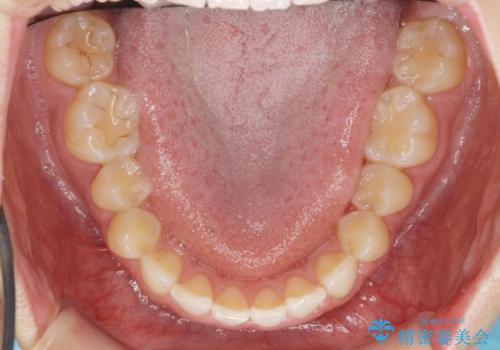

出っ歯に見える前歯の改善 部分ワイヤーとマウスピース矯正

- 出っ歯に見える前歯の改善を希望され、来院されました。

マウスピースでは改善の難しい歯の動きを部分ワイヤー矯正で整えたのち、奥歯の噛み合わせや細かい歯の並びをマウスピース矯正インビザラインで整えていきます。

最終的な前歯の並びに大変満足いただくことができました。